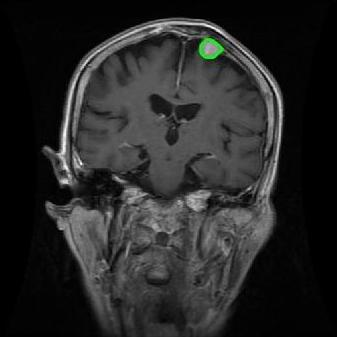

4.2 Comparison with brain tumor MR images segmentation

Brain tumor MRI images represent a critical challenge within the field of medical image analysis, making them a focal point of our research. Various level set models for image segmentation have been applied to brain tumor MRI images, and it is essential to consider the unique characteristics of these images. To validate the excellent performance of the RefLSM, we conduct segmentation comparison experiments on brain MR images and compute the Dice coefficient and Precision values for all evaluated models.

Fig. 4 displays the visual comparison results for segmenting eight brain tumor MR images between the RefLSM and three representative models: the RESLS [8765635], ALF[MA2019201], and L1 model[LIU2019193]. These images exhibit severe intensity inhomogeneity and noise attributable to inconsistent bias field and imaging equipment. The initial level set function (LSF) initialization was consistent across all models, as shown in Fig. 4 (a), which illustrates the initial placement of the zero level contour. For visual clarity, we included the ground truth in Fig. 4 (f). The segmentation outcomes from the RESLS, ALF, and L1 methods are presented in Fig. 4 (b), (c), and (d), respectively.

It is evident from the first and last columns of Fig. 4 (b) that the ALF model tends to become trapped in local minima under severe intensity inhomogeneity. Furthermore, segmentation results presented in the columns 1-4 of Fig. 4 (b) and (c) reveal that both the ALF and L1 models mistakenly segment small isolated or irrelevant regions due to the effects of irregular intensity patterns. Additionally, when weak boundaries are present, as seen in the 1st and 3rd columns of Fig. 4, the RESLS, ALF, and L1 methods fail to accurately identify object boundaries. Consequently, the zero level contours of these models deviate significantly from the objects throughout the level set evolution, causing drastic misalignment after further iterations.

In stark contrast, our proposed method exhibits greater robustness against images exhibiting severe intensity inhomogeneity and weak boundaries. The proposed prior constraint term effectively corrects for intensity inhomogeneity, while the proposed binary level set adeptly reduces noise during the segmentation process.

Overall, these findings demonstrate that the segmentation outcomes produced by our model are more accurate. Besides visual assessment, we calculate the Dice and Precision values of evaluated models for brain tumor segmentation in table 1. Based on these results, we draw a boxplot with scatterplot overlay, as shown in Fig. 6, which displays the data distribution and facilitates comparison of different models’ performance across various brain tumor MR images. We analyze the maximum, median, and minimum, which correspond to the best, median segmentation results, and worst segmentation results, respectively. It is clear that the RefLSM achieves more accurate segmentation results compared to the other models. Moreover, the smaller range of the RefLSM in the boxplot indicates robustness and stability to different images of the brain tumor.